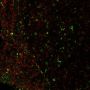

Applikationen IF, IHC

IF (verified), IHC, FFPE (verified)

This antibody recognizes a glycoprotein of 110 kDa, which is identified as CD68. It is important for identifying macrophages in tissue sections. It stains macrophages in a wide variety of human tissues, including Kupffer cells and macrophages in the red pulp of the spleen, in lamina propria of the gut, in lung alveoli, and in bone marrow. It reacts with myeloid precursors and peripheral blood granulocytes. It also reacts with plasmacytoid T cells, which are supposed to be of monocyte/macrophage origin. It shows strong granular cytoplasmic staining of chronic and acute myeloid leukemia and also reacts with rare cases of true histiocytic neoplasia. Lymphomas are negative or show few granules.

IF (verified)|IHC (FFPE) (verified)

Higher concentration may be required for direct detection using primary antibody conjugates than for indirect detection with secondary antibody|Immunofluorescence (direct conjugate): 1-5 ug/mL|Immunohistology (formalin) 2-4 ug/mL|Staining of formalin-fixed tissues is enhanced by boiling tissue sections in 10 mM citrate buffer, pH 6.0, for 10-20 min followed by cooling at RT for 20 minutes|Flow Cytometry 0.5-1 ug/million cells/0.1 mL|Optimal dilution for a specific application should be determined by user